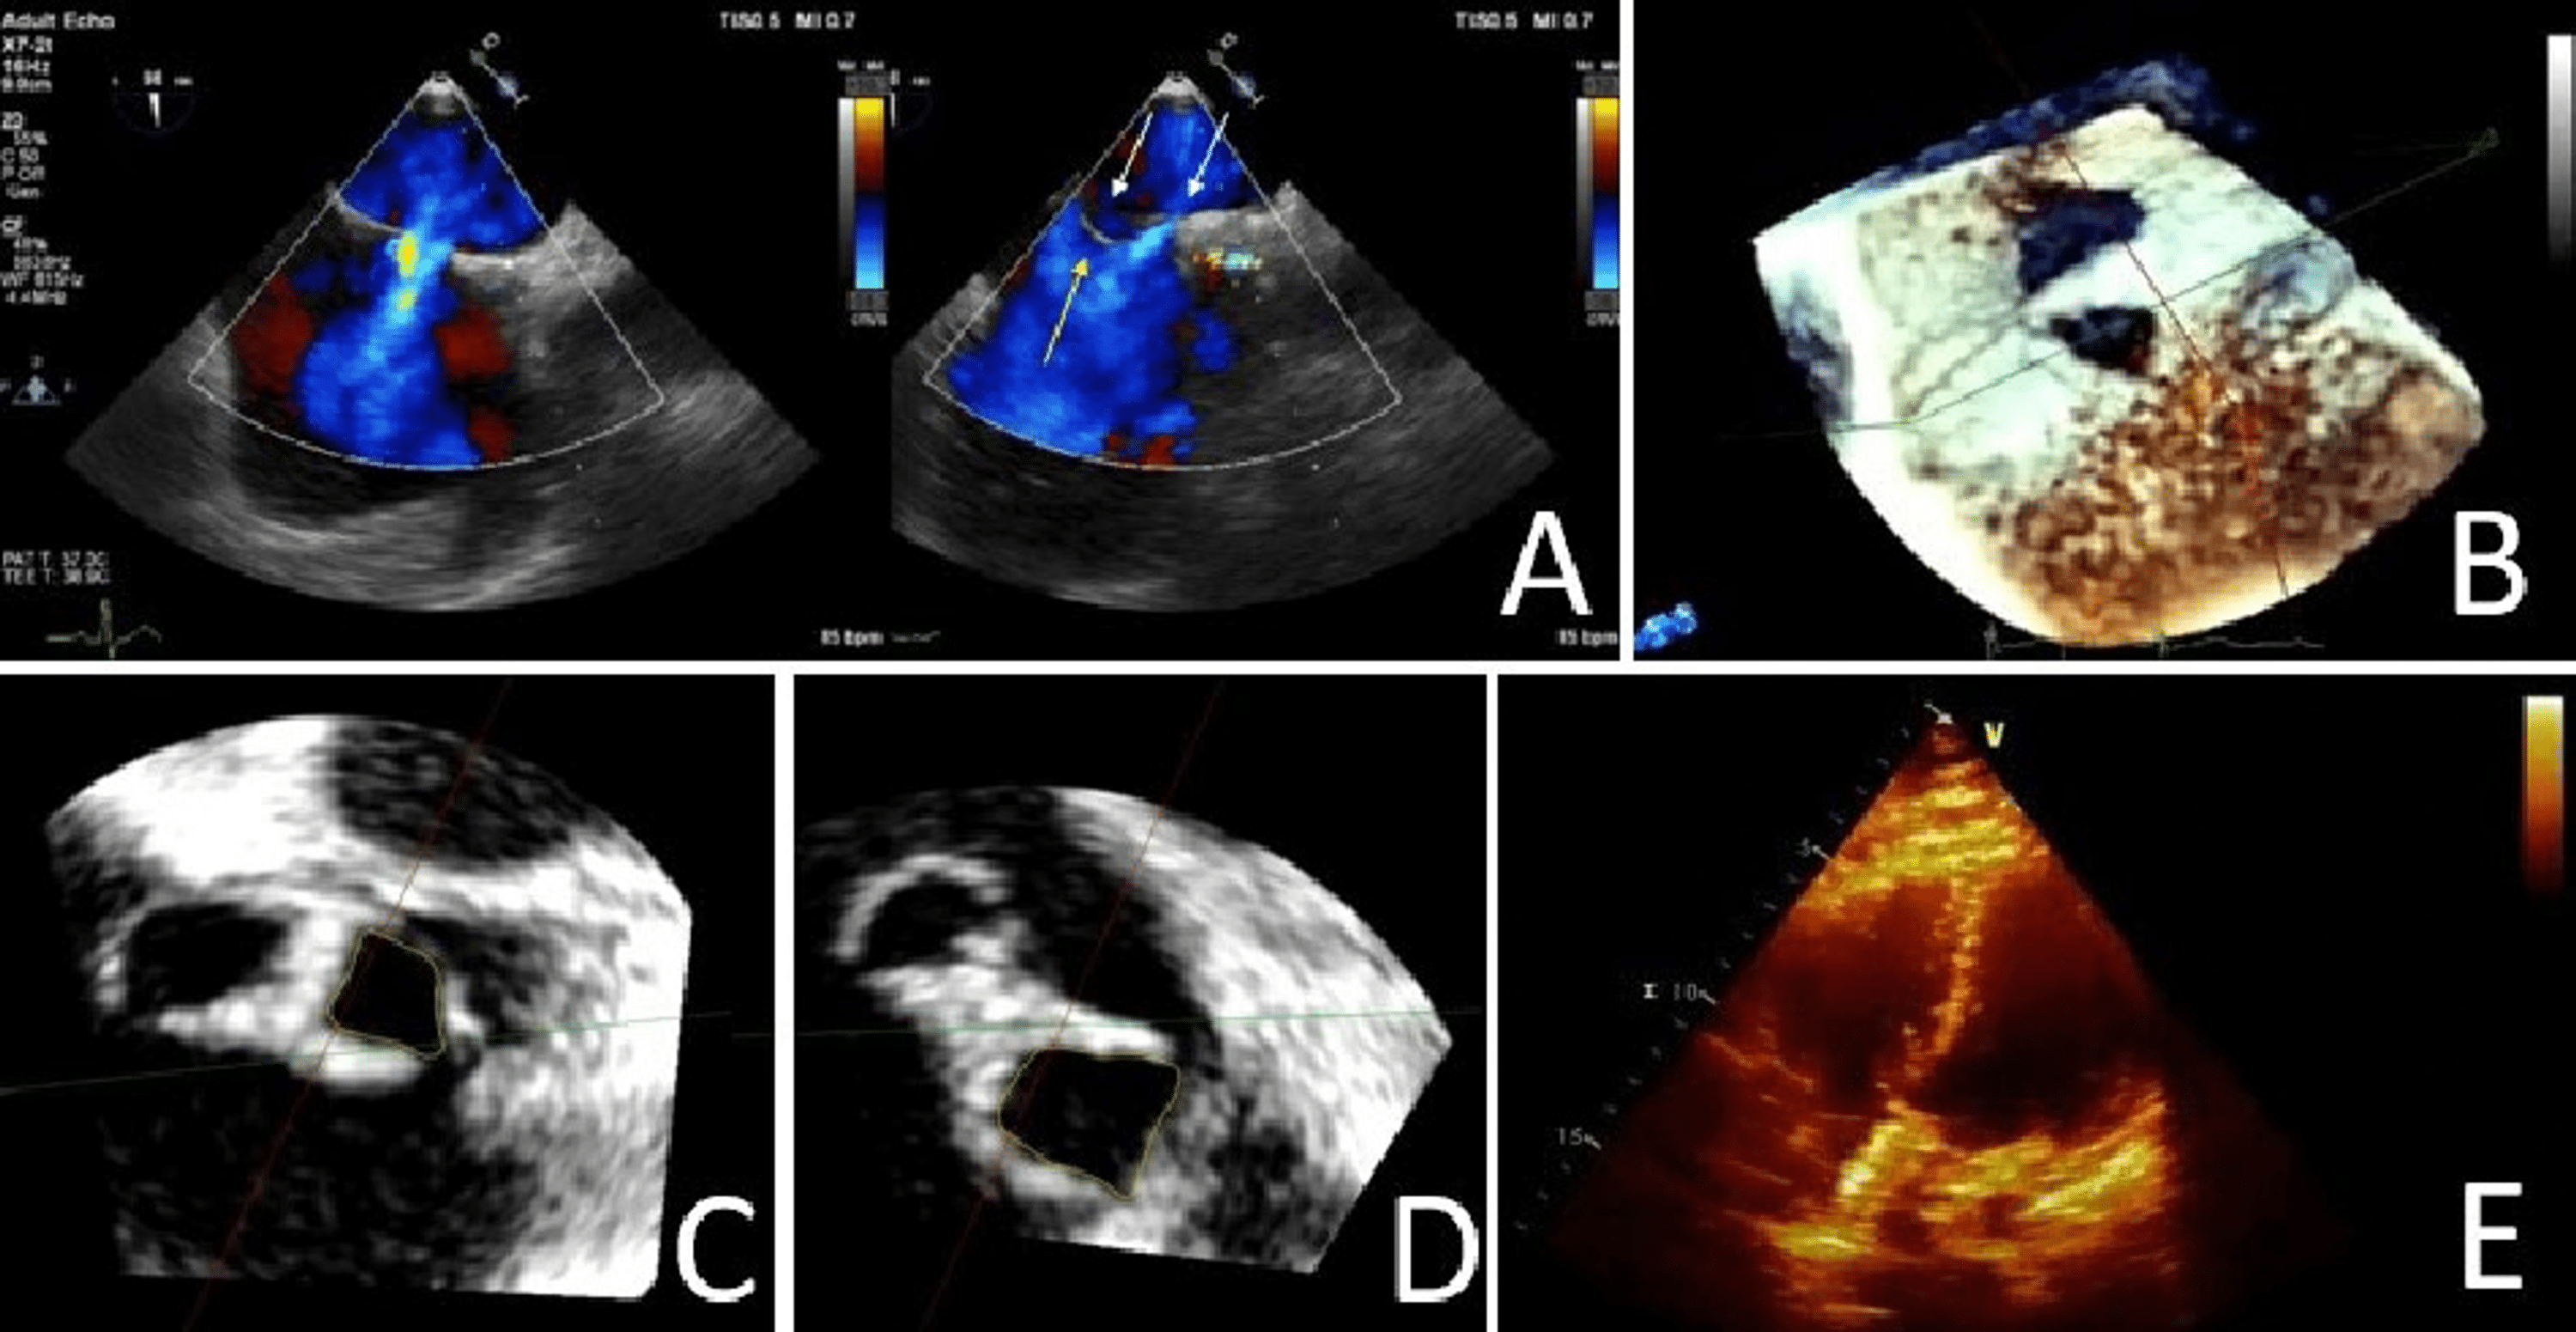

ThreeDimensional Cardiac Imaging A Necessity to the Diagnosis and Swiss Cheese Pattern Endometrium  We found gynecologic conditions such as submucosal leiomyoma with degeneration, endometrial polyp,.    — endometrial hyperplasia with atypia (endometrial intraepithelial neoplasm) histology:  to uncover gynecologic conditions with similar transvaginal sonographic findings of thick uterine endometrium with.    — the cut surface of the endometrium may have a “swiss cheese” appearance caused by cystic dilatation of.    — the thorough. Swiss Cheese Pattern Endometrium.